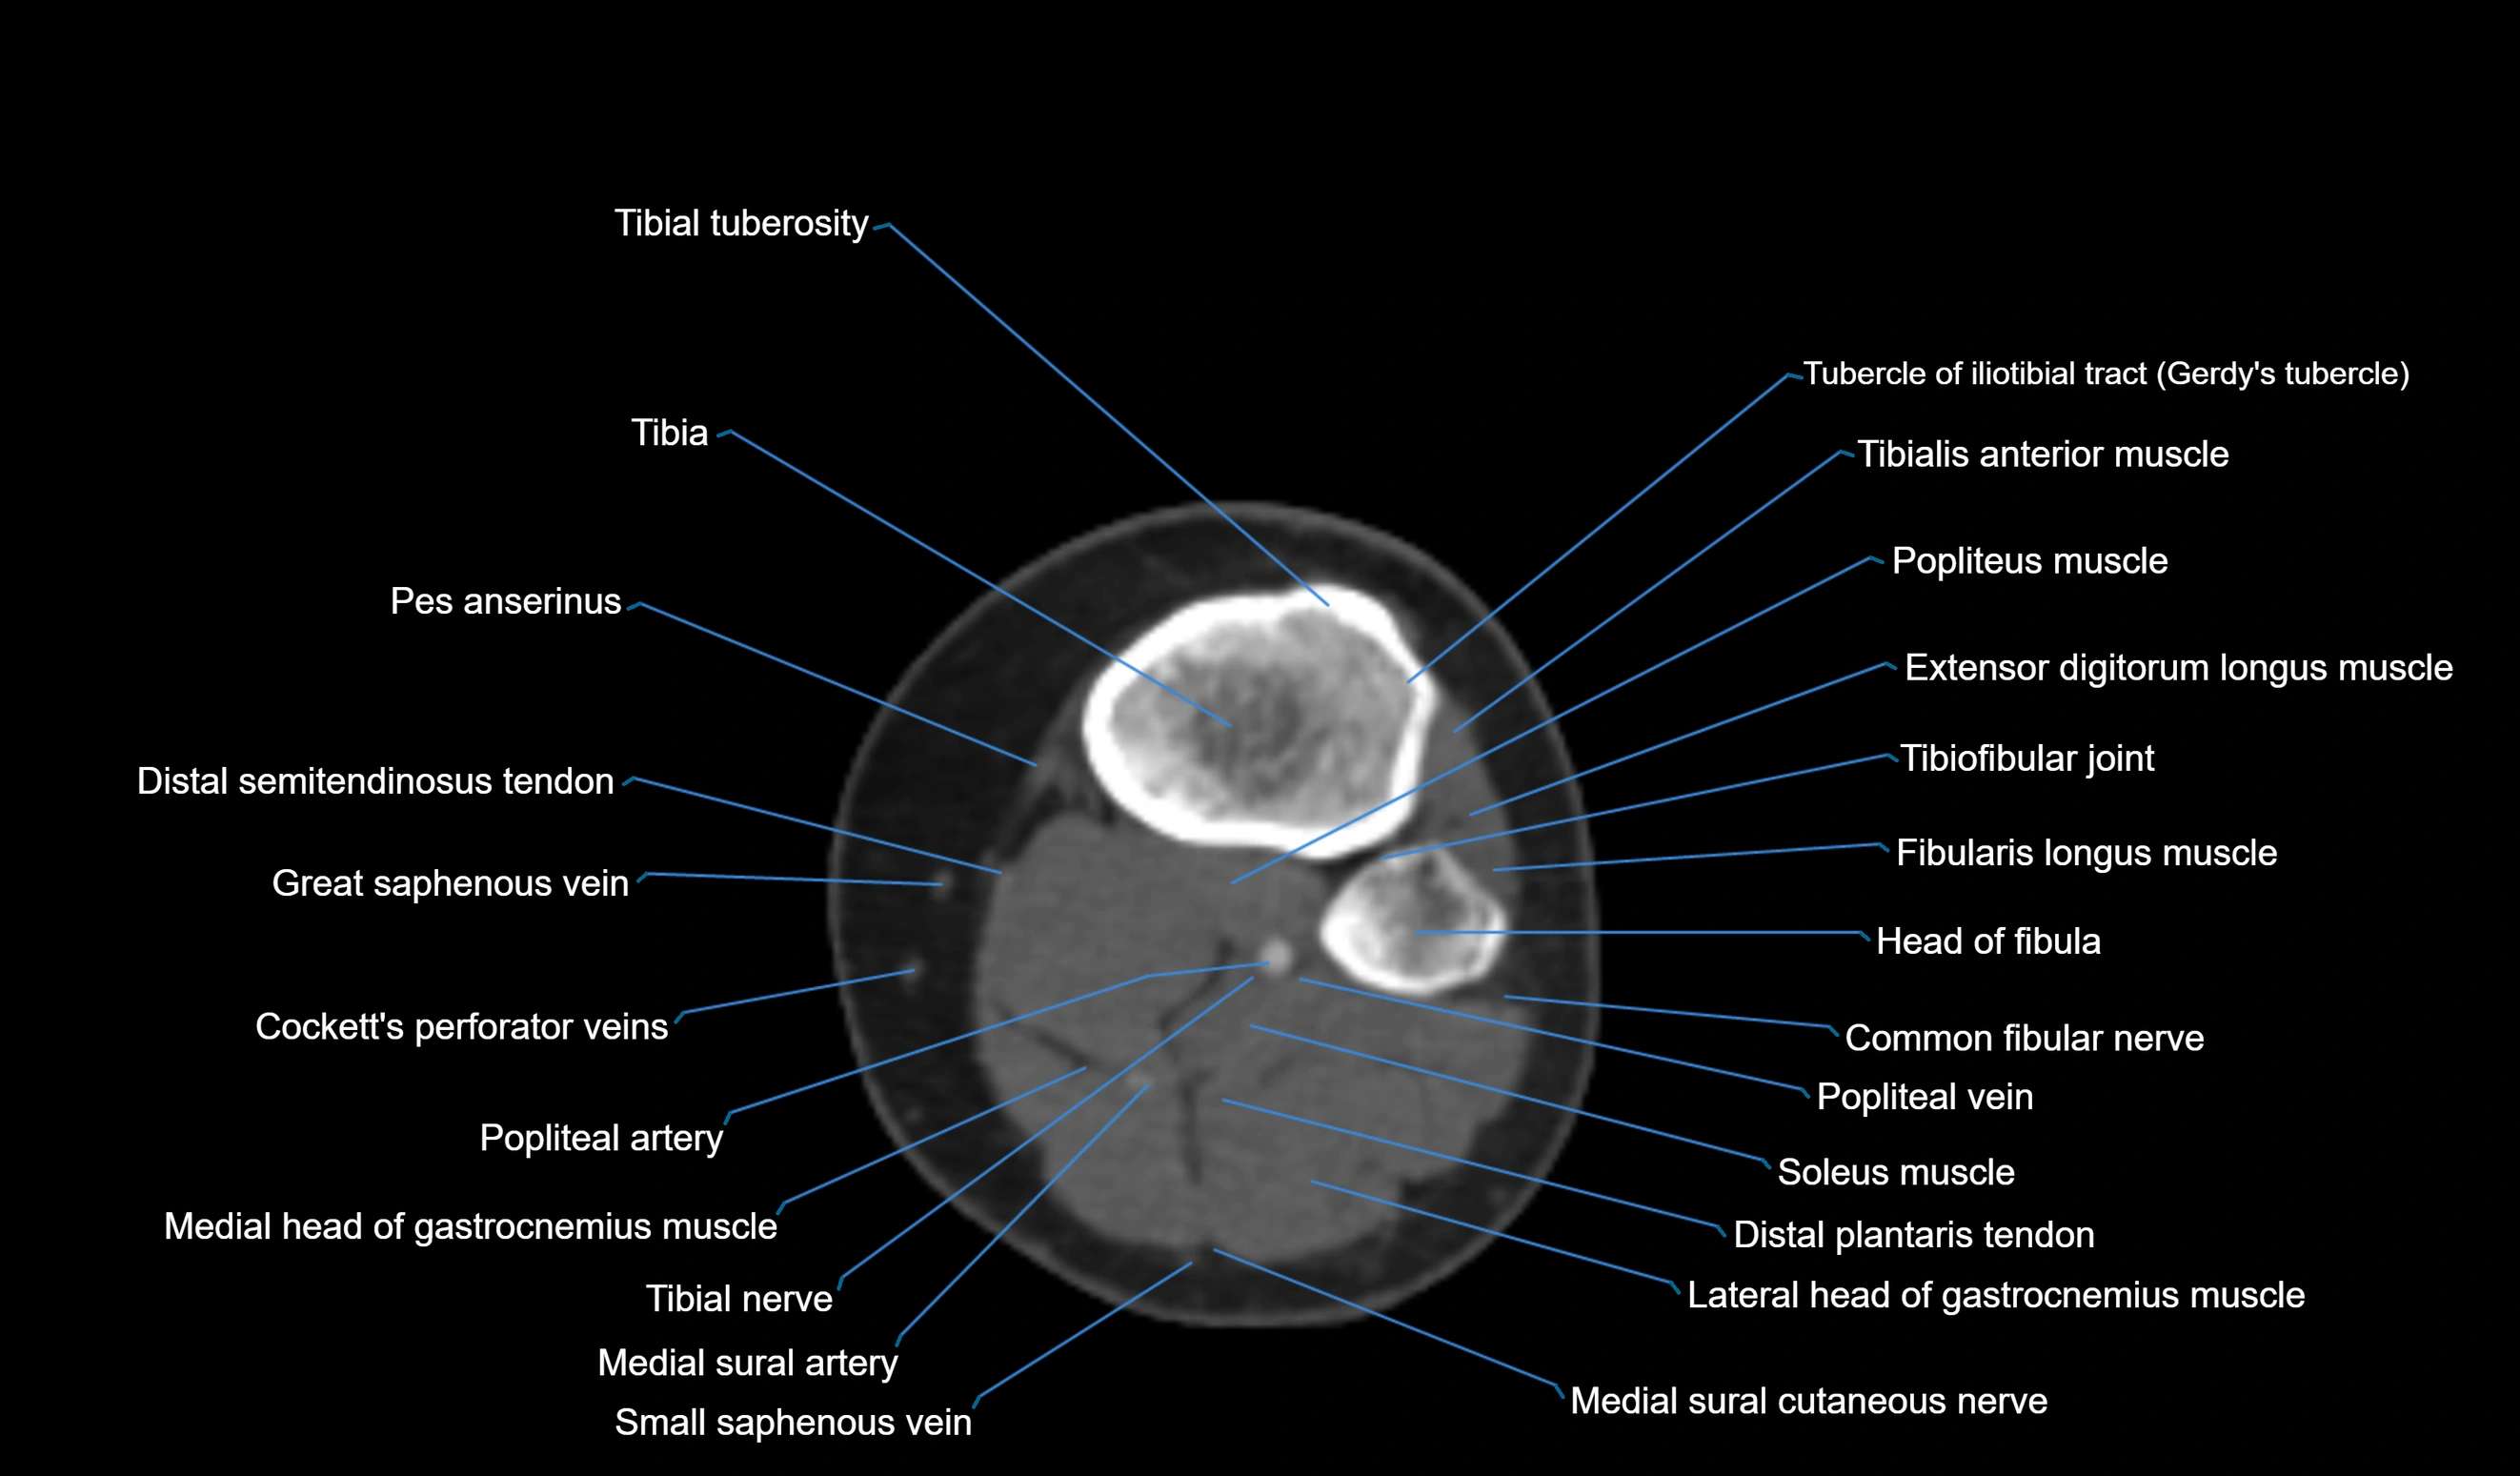

- Common fibular nerve

- Extensor digitorum longus muscle

- Fibularis longus muscle (peroneus longus muscle)

- Gerdy’s tubercle

- Head of fibula

- Lateral head of gastrocnemius muscle

- Medial head of gastrocnemius muscle

- Plantaris muscle

- Popliteal artery

- Popliteal vein

- Small saphenous vein

- Soleus muscle

- Superior tibiofibular joint

- Tibia

- Tibial nerve

- Tibial tuberosity

- Tibialis anterior muscle

- Tibiofibular joint (proximal)